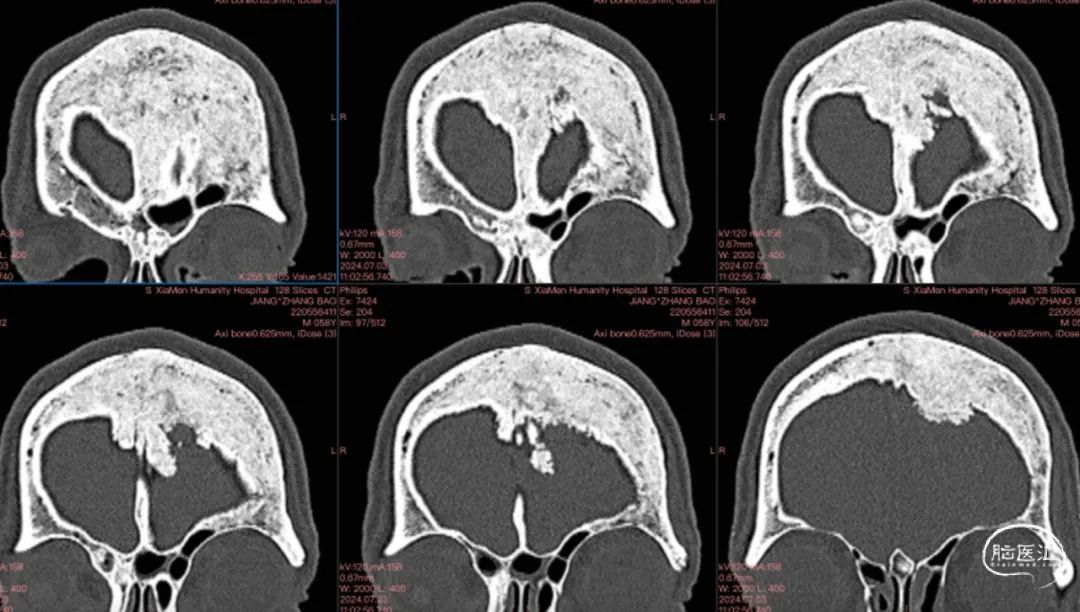

CT

左额内外板可见骨质增生